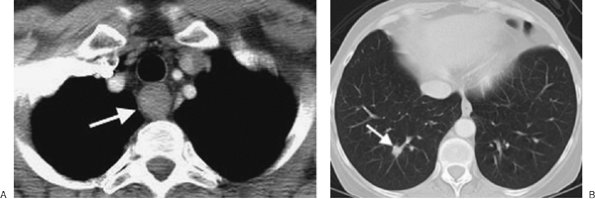

FIGURE 6-19. Esophageal carcinoma. A: CT scan of a 54-year-old woman with dysphagia shows a circumferential mass involving the upper esophagus (arrow). Note the lack of air within the thick-walled esophagus. B: CT scan at a level inferior to (A), with lung windowing, shows a parenchymal metastasis (arrow).

FIGURE 6-20. Esophageal carcinoma. CT scan of a 63-year-old man shows a distal esophageal mass (E). The man also had a cavitary squamous cell carcinoma in the right lower lobe (arrow).